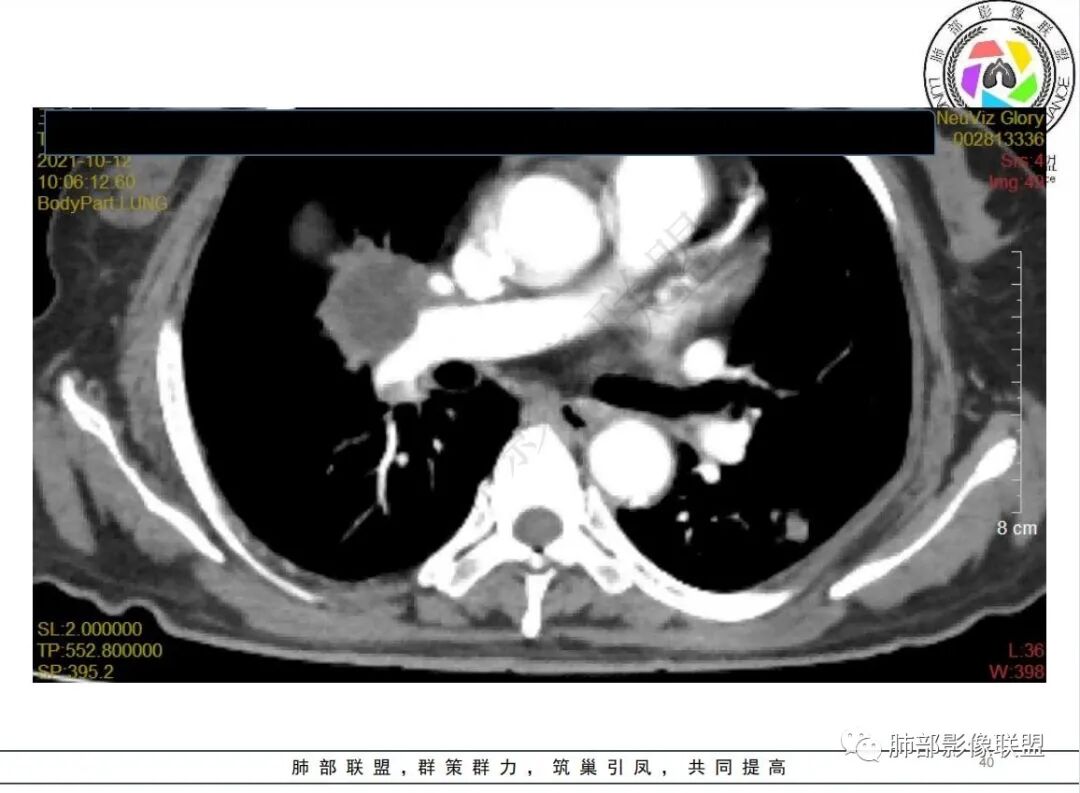

白血病化疗后,出现多发结节,边缘可见晕征,病灶内可见多发坏死,右肺中叶肺动脉可见充盈缺损,右肺中叶可见融冰征,考虑毛霉菌,右肺中叶肺动脉栓塞伴右肺中叶肺梗死。

有白血病病史,免疫妥协,双肺多发结节,纵隔增大淋巴结,短期抗炎治疗后复查,病灶明显增大,右肺门肿块,内可见坏死,临近肺动脉受侵,支气管闭塞,周围见阻塞性炎症,考虑感染性病变,毛霉菌可能大

4.白血病化疗后,CT上出现多发结节,边缘可见晕征,病灶内可见多发坏死,右肺中叶肺动脉可见充盈缺损,右肺中叶可见融冰征,右肺中叶肺动脉侵犯栓塞伴右肺中叶肺梗死,可符合真菌感染。

血管侵袭性曲霉病是最常见的类型,其特征是真菌菌丝侵入和阻塞中小肺动脉,形成凝固性坏死、肺泡出血或出血性梗死。

6.肺曲霉病典型的CT表现是结节周围有磨玻璃样的晕征表现,或胸膜为宽基底的楔形实变。晕征表现为曲菌感染的肺结节伴梗死和凝固性坏死,周围有肺泡出血。最终可出现空泡征象,并可观察到中央坏死组织与周围肺实质分离形成空气新月征。